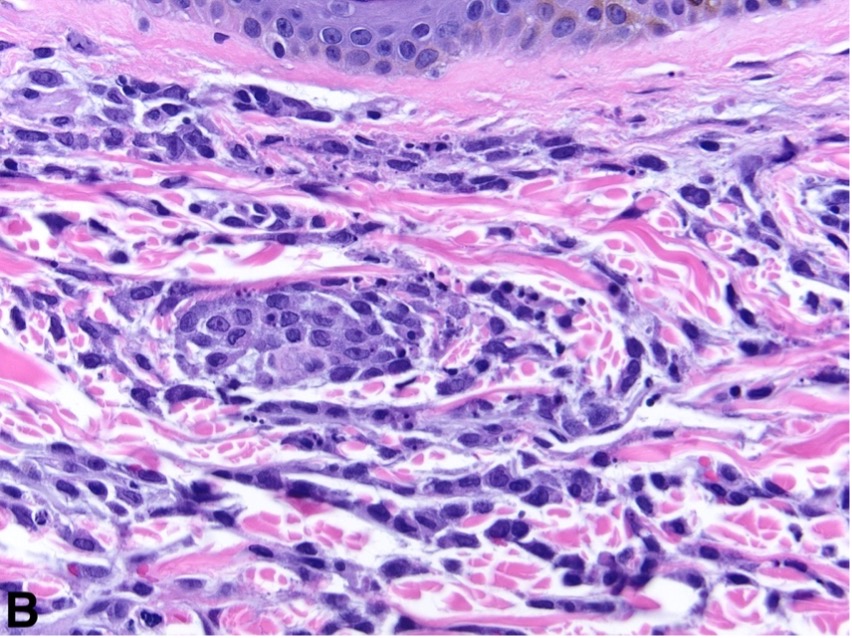

Figure 2. Pink papules overlying the patient’s pacemaker on his left chest.Diagnostic testing. Skin biopsy revealed a diffuse interstitial infiltrate composed of myeloid cells (Figure 3AB). A complete blood count with differential revealed pancytopenia with 60% monocytes and a macrocytic anemia (normal range, 2-8%). A subsequent peripheral blood smear showed atypical monocytoid cells. Bone marrow biopsy revealed > 95% blasts.

Figure 3A-B. A. Hematoxylin and eosin (H&E) 20x objective magnification and B. H&E 40x objective magnification are shown. Diffuse interstitial infiltrate composed of atypical myeloid cells consistent with leukemia cutis.